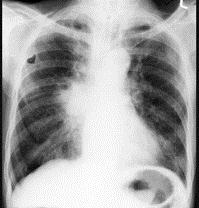

问题 72岁,男,呼吸急促、气喘4个月,请结合胸片和CT,选出最可能的诊断 ( )

选项 A、韦格肉芽肿 B、支气管腺瘤 C、错构瘤 D、肺结核 E、肺癌

答案 E